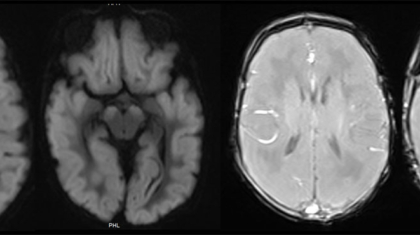

9-year-old female with URI for 1 week, fever for 3 days, seizures and altered sensorium for 1 day.